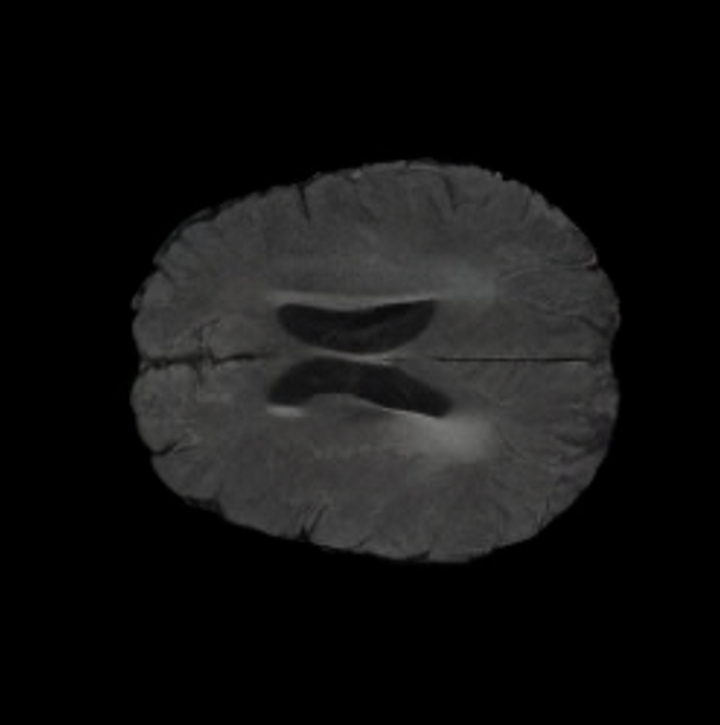

Tumour Information Preservation. For the brain tumor segmentation, we use a Swin UNETR model[28, 70], trained with random rotation, and intensity as data augmentation. On the test set with human ground-truth annotations (), the brain volumes generated from single slice input preserve the volume of the different tumour components (paired t-test, for all 3 classes). In Figure 4, we highlight the tumor profiles of the generated MRIs compared to the ground truth tumour profile. The real MRI Dice score in the test set is 85.15 while the generated MRIs from a single slice have a dice score of 83.09. This shows how the generated MRIs indeed preserve the tumor information and can act as an affordable and informative pseudo-MRI, before conducting an actual costly MRI examination in hospitals. More detailed results are provided in supplementary material.

On the test set with human ground-truth annotations (), the brain volumes generated from single slice input preserve the volume of the different tumour components (paired t-test, for all 3 classes) (see Table I). The real MRI Dice scores are put for reference to our generated MRIs. X-Diffusion outperforms baselines TPDM [39] and ScoreMRI [19] in tumour preservation (see Table I and Figure III). We ran experiments comparing the tumour segmentation Dice Score varying X-Diffusion configurations. The multi-slice input X-Diffusion achieves marginally better Dice Score than the single slice input model (83.47 83.09). We also ran experiments with slice input used for volume reconstruction intersecting or not with tumour. We observe on average a drop of 6% Dice Score (see Table I). Further away from the tumour the input slice for volume reconstruction is selected, we observe a linear decrease in tumour segmentation Dice Score with lowest value of 77.21 Dice Score (see Figure VI).

This shows how the generated MRIs indeed preserve the tumour information and can act as an affordable and informative pseudo-MRI, before conducting an actual costly MRI examination in hospitals. Given that our model has been trained on brain scans all with tumours, we expect to see hallucinations of tumours in healthy scans. We report two cases of failure of our model in Figure VII. Hallucinations of tumours on healthy samples represent 2% of the test set.